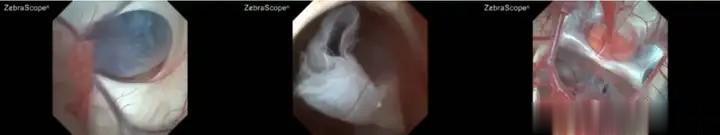

肖庆主任建议采用软性神经内镜手术来解决囊肿问题。软性神经内镜手术具有创伤小、视野清晰、可灵活到达病变部位等优势,骨孔直径不到 1cm。在完善脑电图等检查后,于既定手术日,肖庆主任团队为小妍在全麻下行神经内镜检查术 + 脑室 - 囊肿 - 基底池造瘘术,术后病情平稳,复查MRI显示:脑室回缩、囊肿塌陷,于术后一周好转出院。

软性神经内镜技术在治疗鞍上池囊肿引发的梗阻性脑积水方面具有显著优势。首先,它能够通过一个微小的骨孔,灵活地到达颅内各个部位,对囊肿进行精准的探查和处理。在手术过程中,医生可以清晰地观察到囊肿的位置、大小以及与周围脑组织和脑脊液循环通路的关系,从而制定个性化的治疗方案。

其次,软性神经内镜手术不仅可以切除囊肿壁,还可以通过造瘘术将囊肿与脑室或脑池相通,重建脑脊液的正常循环通路。这种手术方式不仅能够有效解除囊肿对脑脊液循环的阻塞,还能避免传统分流术可能出现的并发症,如分流管堵塞、感染等。此外,软性神经内镜手术还可以结合其他技术,如脉络丛烧灼术,进一步减少脑脊液的分泌,提高治疗效果。